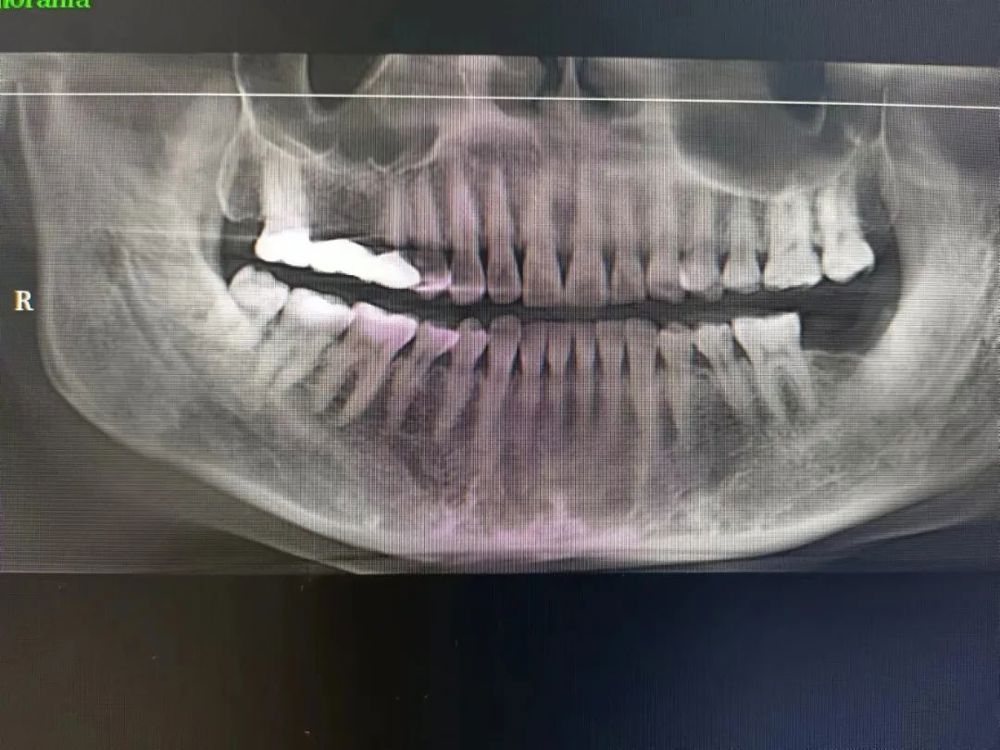

三、種植牙技術

目前,社會上很多人被牙齒缺失所困擾,牙齒缺失不但影響人的咀(jǔ)嚼和語言功能,對於人的麵部美觀也是一種(zhǒng)影響,甚(shèn)至有些人因缺失牙齒而不願意張口說話,種植牙被譽(yù)為人類“第三副牙齒”,因其舒(shū)適、美觀、功能好而被缺牙患者追捧。經衛建委批準,我院(yuàn)於2023年3月18日正式開展種植牙技術,開展當天門診手術7例共計14顆植體,術後1天回訪患者表示無紅(hóng)腫、無疼痛症狀,術後7天回(huí)訪一切良好無異常,術後10天拆線創口愈合良好,自(zì)開展口腔種植手術以(yǐ)來(lái),有(yǒu)許多患者紛紛(fēn)到科裏(lǐ)進行相關谘詢和檢查,更是不斷有患者預約意向種植,我院嚴格按照江西省(shěng)醫療保障局、江西省衛生(shēng)健康(kāng)委員會關(guān)於公布實施口腔種植類醫(yī)療服務價格有關事項的通知—贛醫(yī)保字《2023》3號文件執行操作,在(zài)手術診療中,嚴(yán)格操作流程,減少感染風險。我院口(kǒu)腔種植技術的成功和發(fā)展,不僅完(wán)善了傳(chuán)統(tǒng)牙(yá)齒修複技術的不足,而且在功能與美觀上給了人(rén)們嶄新的體驗,我(wǒ)院(yuàn)致力於提供一站式口(kǒu)腔種植診療(liáo)服務,必將為本縣及周邊缺失牙患者找回(huí)美麗、自信的微(wēi)笑。

案例一

種植前 種植後

案例(lì)二